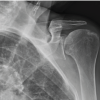

A 24 year old female presented in outdoor patient department with complaints of pain in the left knee of 1 month’s duration. Pain was insidious in onset and increased gradually over a period of 1 month. There was no swelling over the knee joint. There was no history of any significant trauma, fever, cough and night sweats. On clinical examination there was localized tenderness over the tibia just below the joint line. There was no evidence of joint effusion. Passive and active range of motion was within normal limits. There was no evidence of synovial hypertrophy. McMurray’s and Drawer test were negative. An X-ray [Fig. 1&2] of the knee joints (AP and lateral) showed a lytic lesion in the centre of the right tibia in the epiphysis just below the joint line measuring 2*1.5 cm. It was well defined lesion with well defined border and narrow zone of transition. Other bones being normal. MR imaging was suggestive of brodie’s abscess [Fig.3]. Differential diagnosis–brodie’s abscess, tuberculosis, Giant Cell Tumor, Chondroblastoma, Langerhans Cell Histiocytosis, Metastases, Aneurysmal bone cyst, Osseous Lipoma, Osteomyelitis, Subchondral Cyst. Fine needle aspiration cytology was inconclusive. Total leukocyte count was 9400/cmm with 60% of neutrophils and 35% of lymphocyte. ESR was 25 mm by Wintrobe’s method. Since MRI was suggestive of Brodie’s abscess, so needle biopsy or true cut biopsy was not done. Treatment: Since aspiration cytology was inconclusive and MR was suggestive of brodie’s abscess so our treatment was to drain the abscess cavity and fill the cavity with bone graft substitutes. Intra-operatively there was thick sclerotic wall but there was no pus formation. There was soft tissue accumulation which had a yellowish tinge and cavity was found. Tissue was sent for histopathology and culture sensitivity. The cavity was filled with bone graft substitutes. Routine antibiotics were given post-operatively with Gram positive and Gram negative coverage. Histopathology[Fig.4&5]: Report was suggestive of malakoplakia and there was no growth on culture. Histopathology shows sheets of histiocytes and plasma cells in the bone.CD markers study showed positive for CD 68 and negative for CD 138, CD 38 and light chains (kappa and lambda)[3]. Michaelis and Gutman bodies were not seen. Our case was in stage 1 of malakoplakia also called as `early prediagnostic` phase in which there is infiltration with plasma cells and macrophages with absent michaelis and gutman bodies [13].